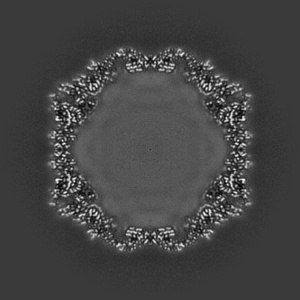

EMD-19774

Coxsackievirus A9 bound with compound 20 (CL300)

Single-particle2.26 Å